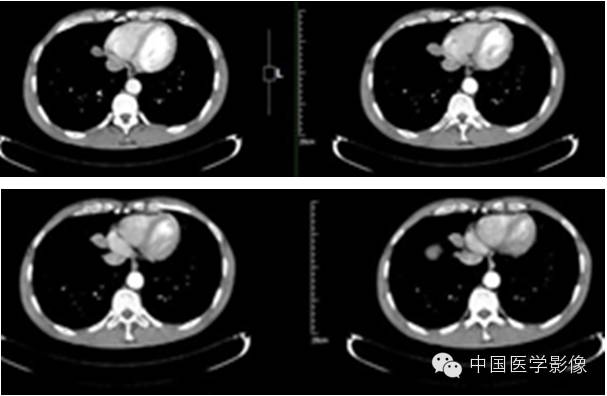

【影像资料】

动脉期

静脉期

延迟期

【病理结果】

孤立性纤维性肿瘤